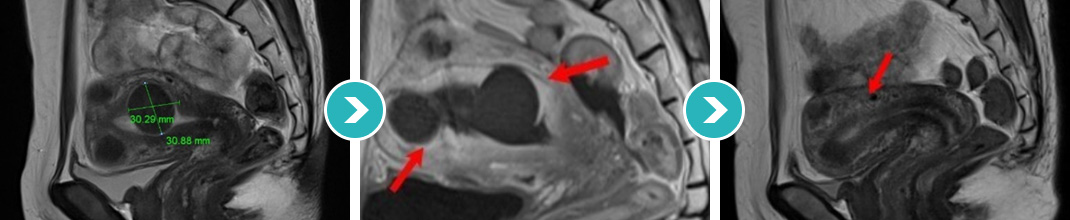

14cm 거대 자궁근종 하이푸 치료 18개월 장기간 추적관찰

4.5cm 자궁근종 하이푸 치료 후 90%이상 괴사, 6개월 추적관찰

점막하 자궁근종 및 2.5cm 근층내 자궁근종 등 다발성 자궁근종 하이푸 치료 후 90%이상 괴사, 6개월 추적관찰

7cm 자궁근종 하이푸 치료 후 90%이상 괴사, 8개월 추적관찰